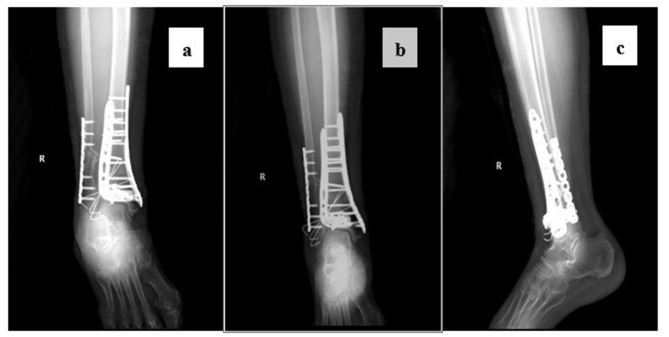

Patients and methods: In this single-center retrospective study, we collected adult (≥18 years old) patients with pilon fractures who underwent open reduction and internal fixation at Xi'an Honghui Hospital from January 2020 to July 2024 and had the cognitive ability to complete the questionnaire. Exclusion criteria included incomplete medical records, concurrent other foot fractures, or severe mental disorders. The preoperative central sensitization (CS) determination criteria were a score of ≥18 on the Chinese version of the 9-item Central Sensitization Inventory (CSI-9). The assessment indicators at baseline and the last follow-up included the Visual Analogue Scale (VAS) for pain, the American Orthopaedic Foot & Ankle Society Hindfoot Score (AOFAS), and the Hospital Anxiety and Depression Scale (HADS). Patients were divided into the CS group and the non-CS group based on whether they had a preoperative central sensitization state, and the differences in baseline characteristics, pain severity, functional performance, and psychological state between the two groups were compared.